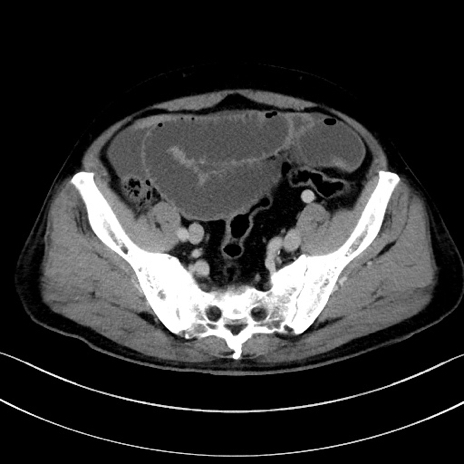

症例15(横断像)

【症例】70歳代男性

【主訴】腹痛

【現病歴】今朝から腹痛あり。全体的に痛い。特に左上の方。排ガスが今日はない。冷や汗が出る。

【既往歴】直腸癌術後

【身体所見】左側腹部〜上腹部に圧痛あり。腹膜刺激症状明らかなではない。軽度反跳痛。左下腹部に術後瘢痕あり。

【データ】WBC 7700、CRP 0.02